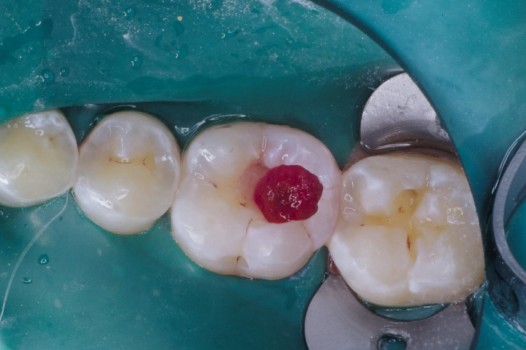

The pits and grooves on the biting surface of teeth often serve as plaque traps and pathways for bacteria to invade the inside of a tooth. This, in turn, leads to the development of cavities. Early diagnosis and treatment arrests the spread of decay and thus prolongs the life of the tooth. Regardless of the size of the affected tooth structure, decay may be swept away with the air abrasion technique and corrected by bonded ceramics, which seal the tooth against further bacterial invasion.